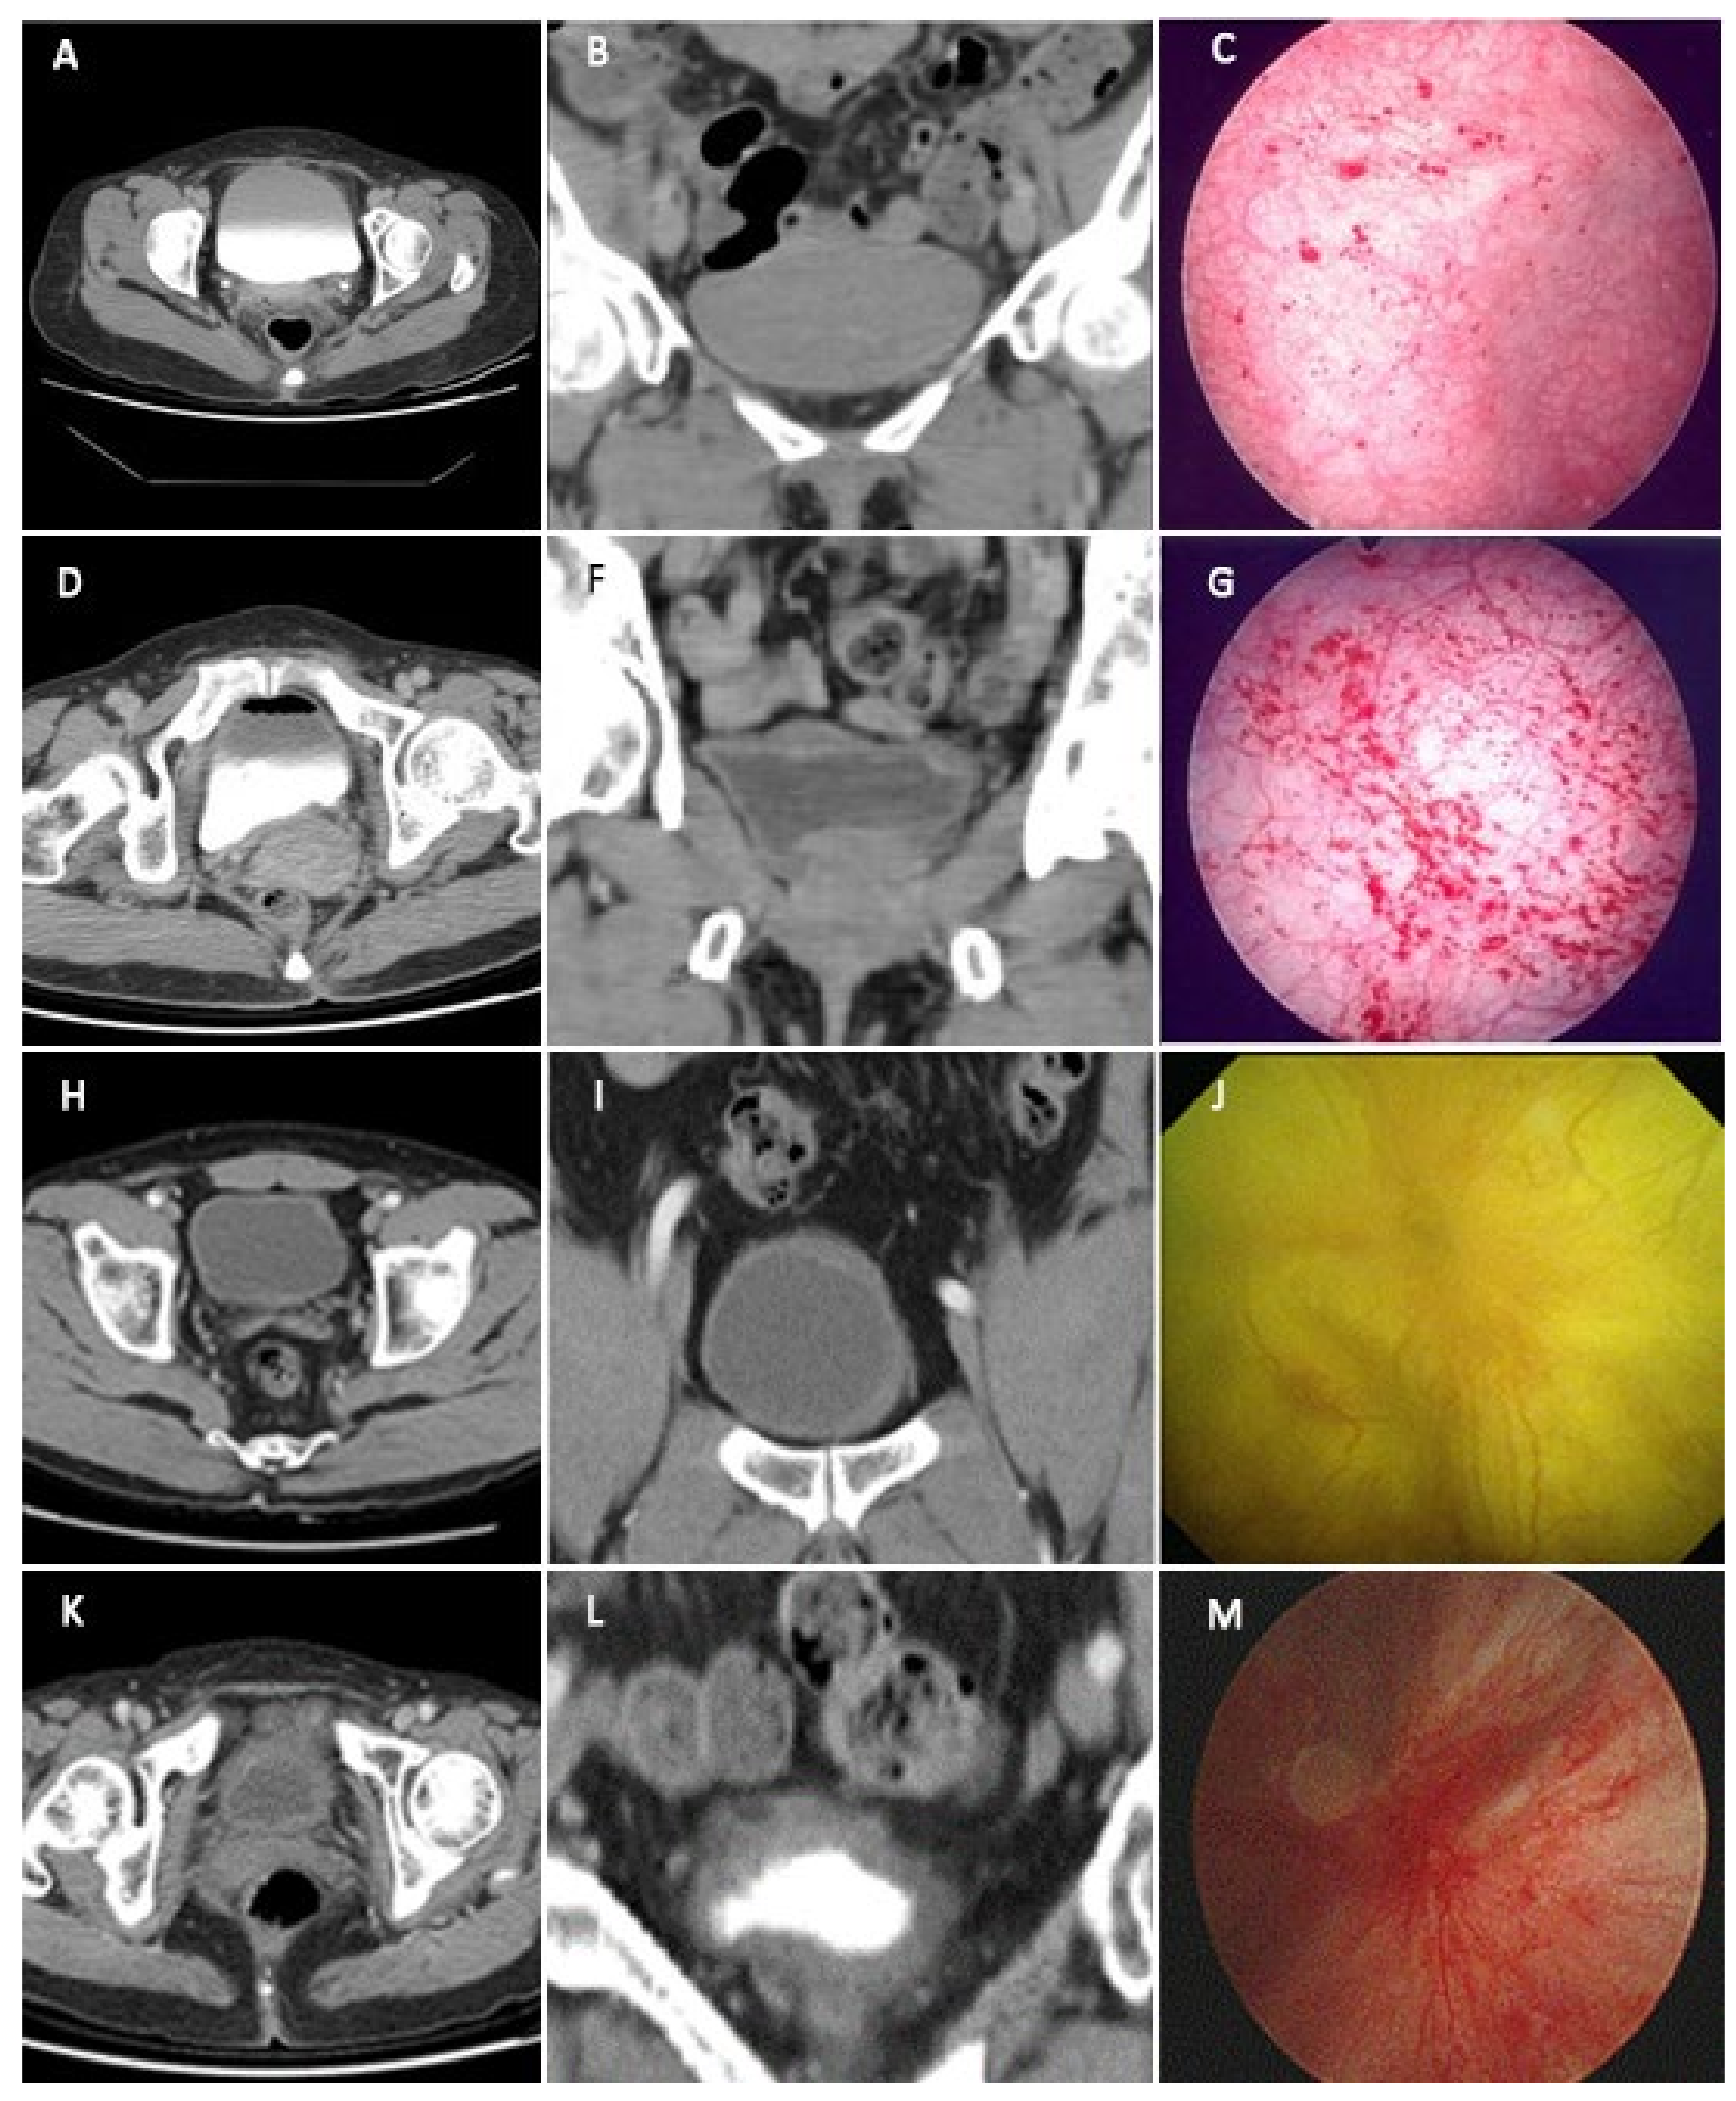

Possible Association between Bladder Wall Morphological Changes on Computed Tomography and Bladder-Centered Interstitial Cystitis/Bladder Pain Syndrome

3. Results